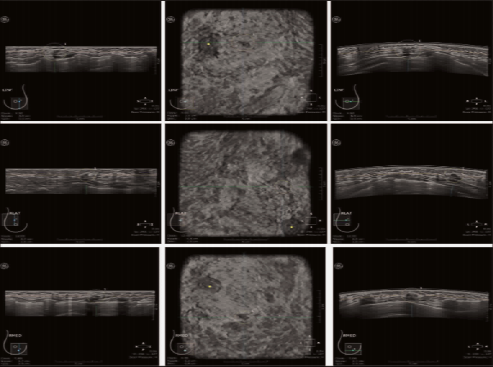

3.工作站阅片一般流程

自动乳腺容积超声阅片区别于常规HHUS的最大特点在于自动乳腺容积超声可获得连续扫查后的全乳容积信息,应用影像数据处理系统经多平面重建(multiplanar reformation,MPR)显示技术重建冠状面及矢状面信息,进行脱机分析;阅片内容包括横切面原始容积数据以及冠状面和矢状面信息,但由于矢状面图像因呼吸运动容易导致一些伪像产生,而仅作参考。

(1)阅片前准备:需要判断图像是否符合质控要求,对于不合格图像需要重新采集;读图前建议优化图像,调整图像窗宽窗位,直至图像显示最清晰,观察层厚建议选择0.5mm。

(2)阅片顺序:建议从AP位冠状面开始,由皮肤层至深部连续读图,主要观察有无肿块、结构扭曲、导管扩张等征象,再重点分析横切面原始图像,按顺序(由上至下或由下至上)连续观察,发现病变的同时将十字交叉对准感兴趣区,进一步从三维平面进行观察,确认病变并排除伪像。

(3)阅片技巧:建议充分利用工作站后处理功能。①图像增益调节,重点观察钙化时推荐将增益调低、提高对比度;②利用局部放大观察肿块细节,如病变内部回声、边缘特征等;③选择多幅不同切面图像同时显示,可以静态观察肿块在不同切面时的形态特征;④选择双侧对照双幅模式观察非对称性病变,如乳腺局部腺体增厚、回声改变病变;⑤灵活使用任意切面旋转功能,观察或获取常规切面难以呈现走行迂曲导管病变。